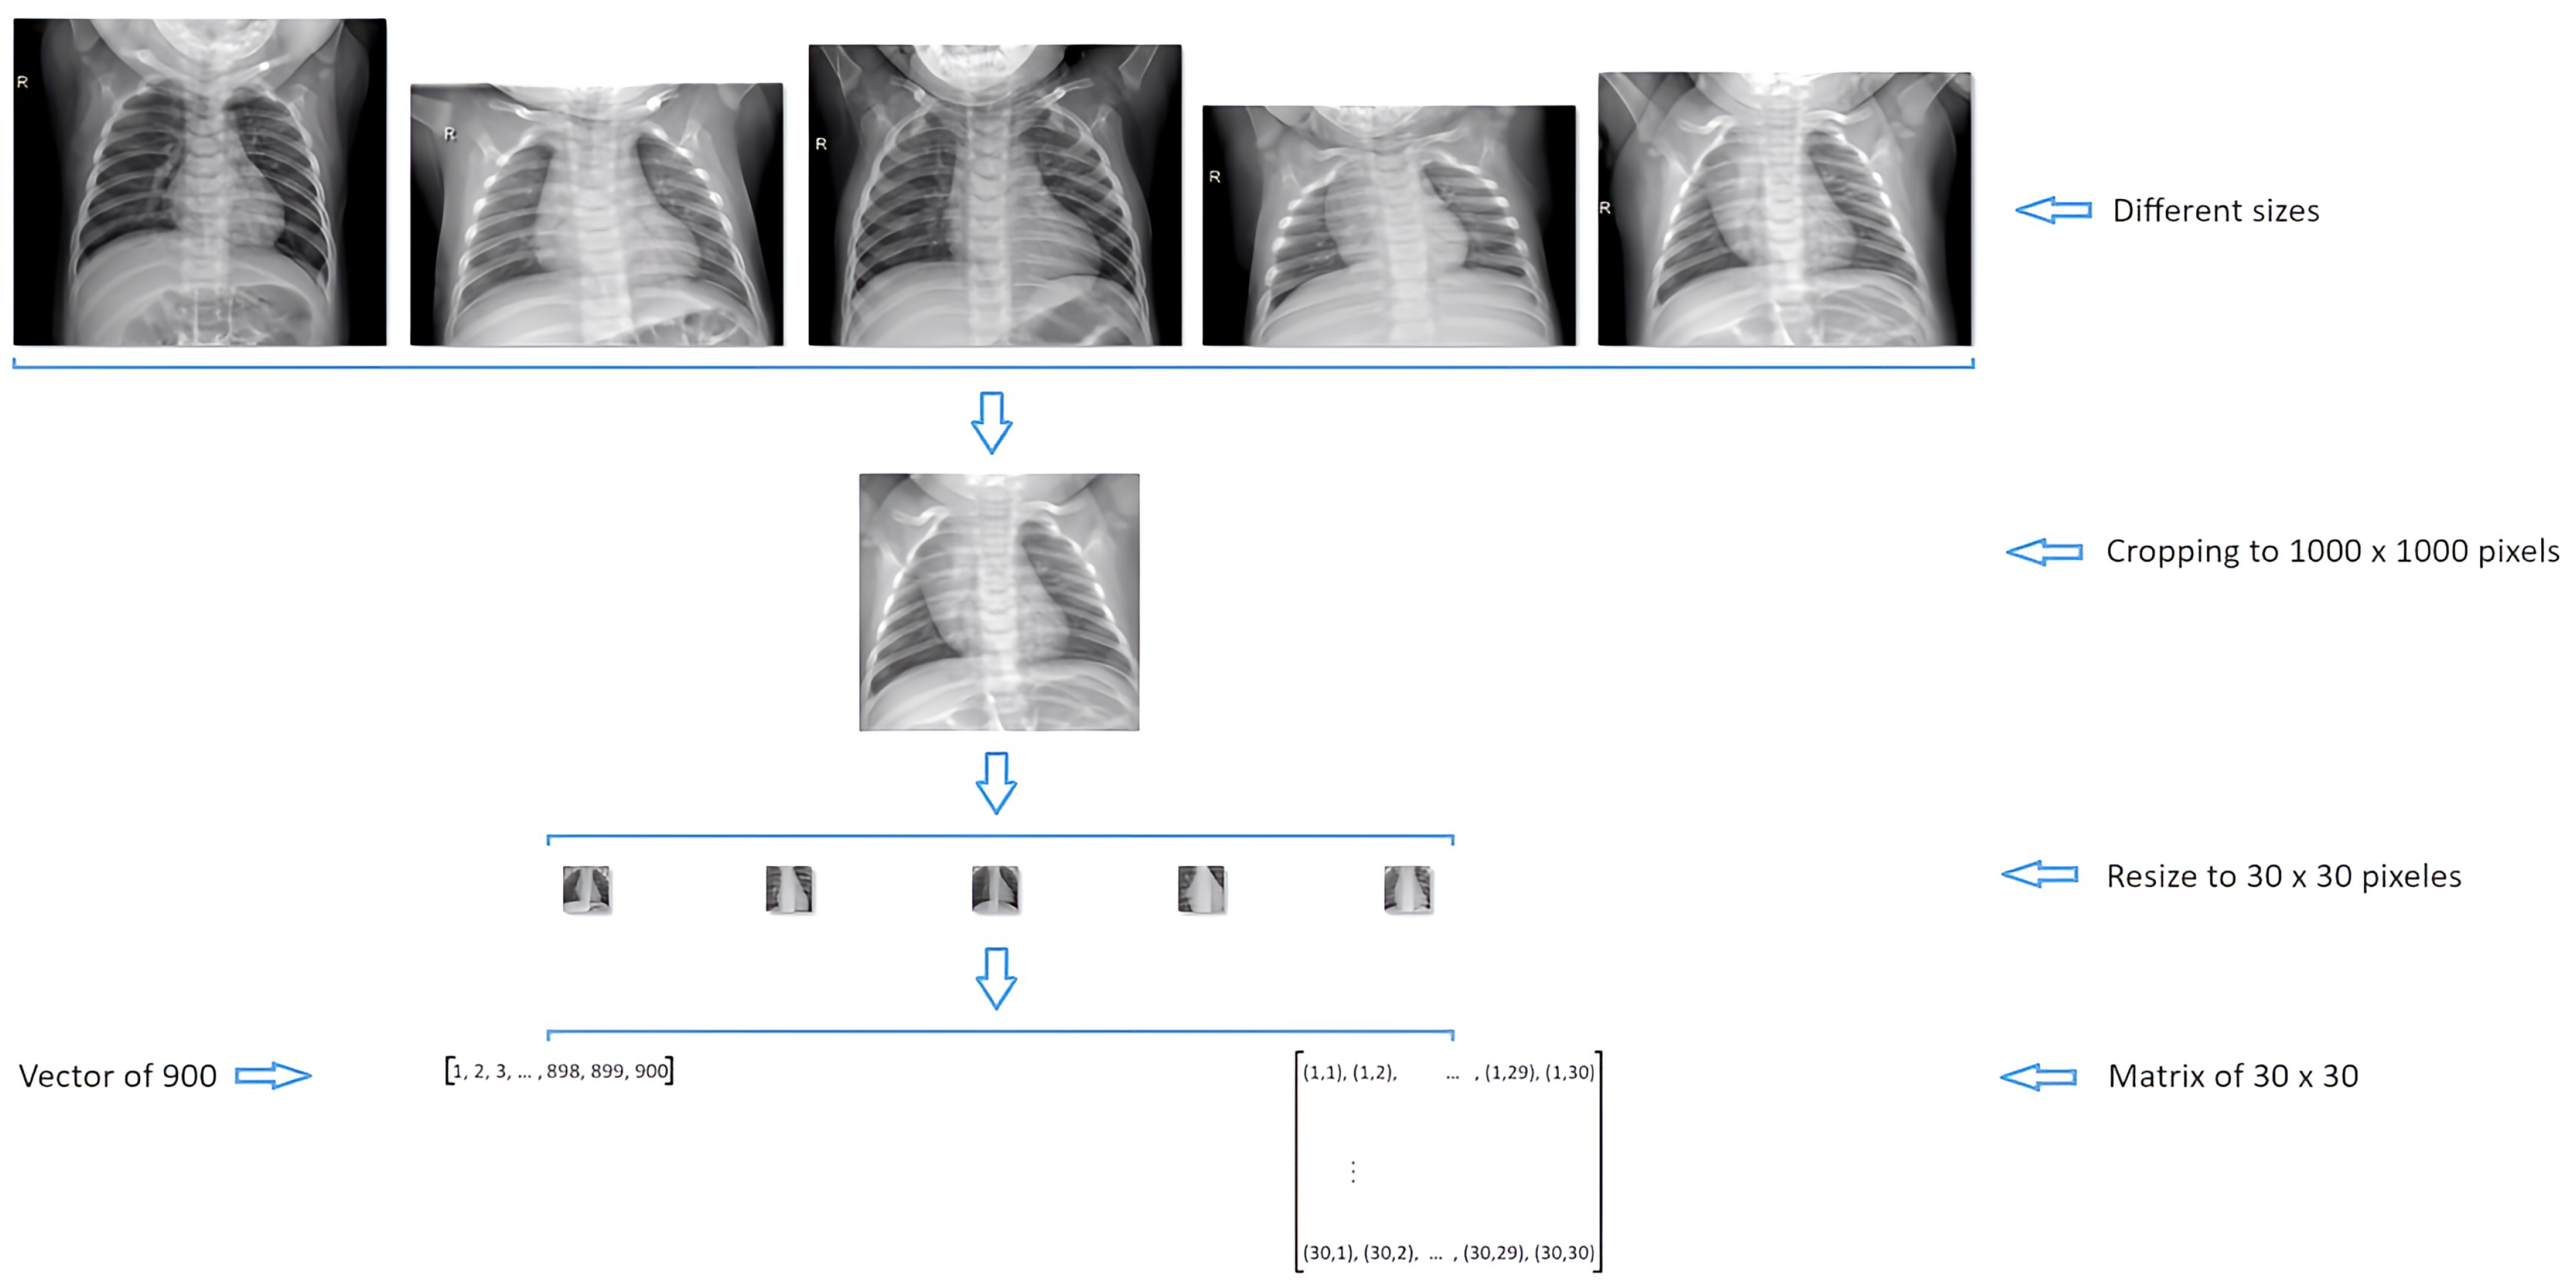

Preprocessing begins with an inspection of the image dataset, revealing 1349 X-ray images of healthy individuals and 3884 images of individuals with pneumonia only in the ”train“ directory. However, not all images have uniform width and height; they exhibit varying proportions, which may result in distortions during resizing.

To address this concern practically, the initial preprocessing involved selecting images with both width and height exceeding 1000 pixels. Figure 5 illustrates the comparison of dimensions between sets of normal and pneumonia images. The use of Figure 6 and Figure 7, providing statistics on the width and height of image sets, aids in the identification of potential selections. The data suggests that images without pathologies (normal) can be chosen from the first quartile, while images with pneumonia are typically selected from around the third quartile. Subsequently, these images were resized to a size of 1000 × 1000, chosen as an average to avoid loss of valuable information from radiographs.

This process results in a dataset comprising 1244 normal images and 881 images with pneumonia. Within the pneumonia category, 393 images are attributed to viral pneumonia and 488 to bacterial pneumonia. Once images are cropped to 1000 × 1000, they are resized to 30 × 30 dimensions. The entire process is illustrated in Figure 8, showing the final transformation applied to the images. This transformation can yield a 900-feature vector or a matrix with a resolution of 30 × 30, depending on the classification model development package used.